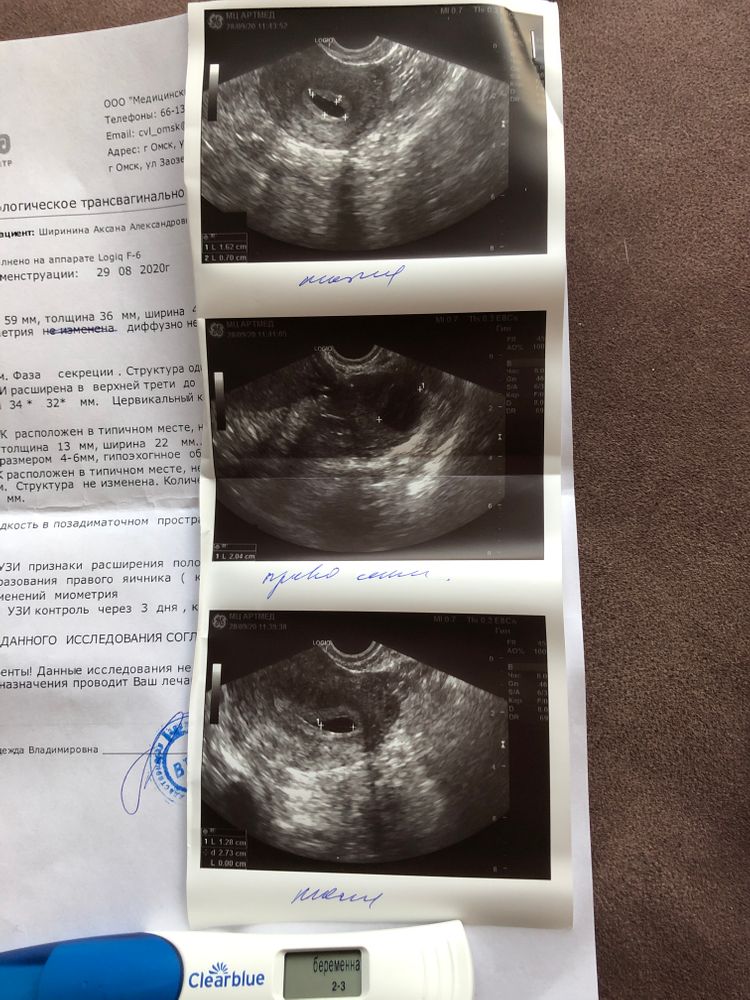

Сходила на узи, думала,исключить внематочную(немного болел живот), но я не то чтобы ответ не получила, мне вобще узистка сказала что беременности точно нет! Ну что за хрень происходит, тесты же полосатятся. Прикрепила два цифровых теста с разницей в несколько дней и узи. Очень нужна помощь.🤦🏽♀️

Узистка говорит делать узи в динамике и ХГЧ.